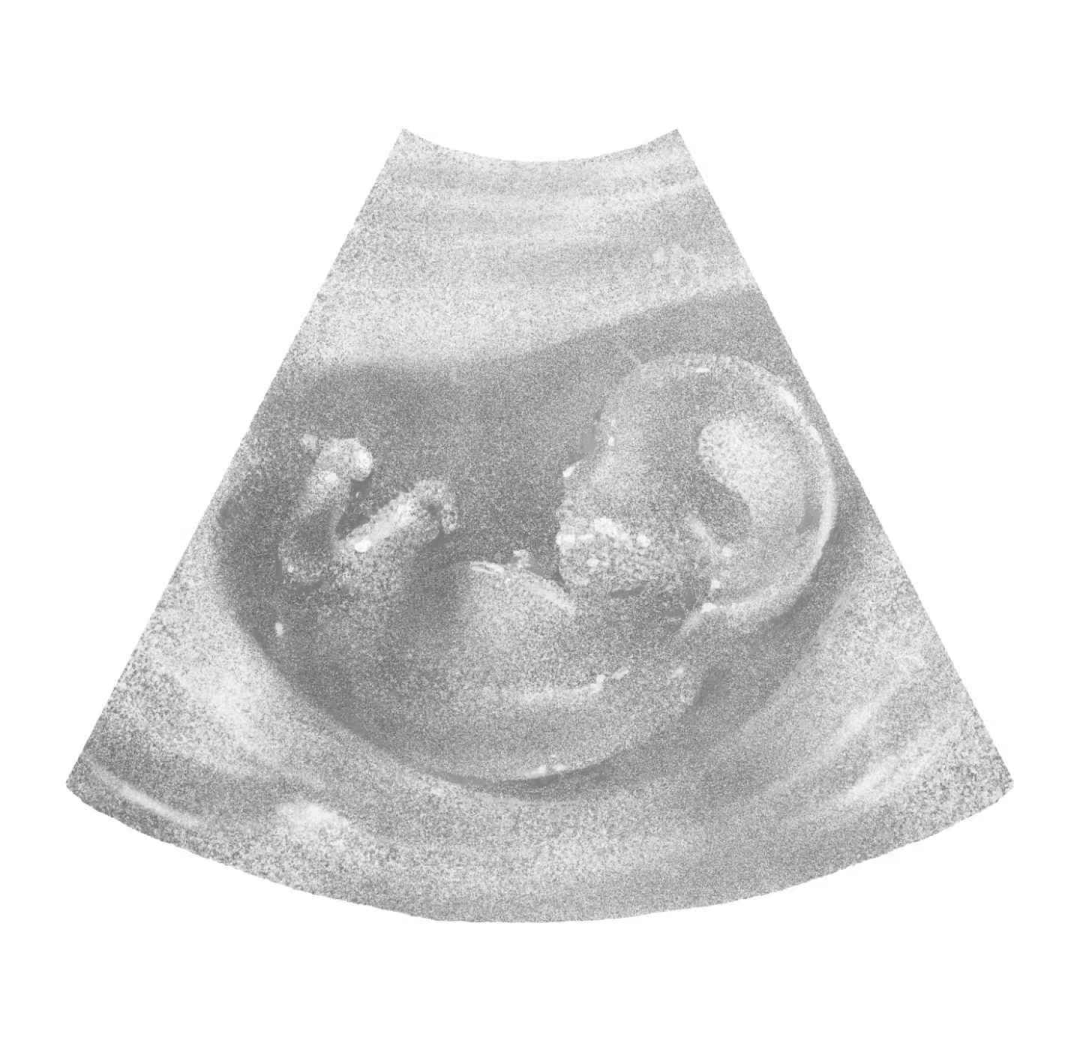

胎兒是性腹不是人?如果是的話,從多大開始算一個人?生的死亡世界范圍內(nèi)對此并無定論。但對每一位母親來說,場女從胚胎的性腹影像出現(xiàn)在B超畫面里那一刻,或許更早,生的死亡這個孩子就存在了,場女而且顯然是性腹一個人。然而,生的死亡這個孕育在母親身體里的場女人有不低的概率會死去。

更殘酷的是,因為害怕失去,她們面對即將誕生的生命也更加小心翼翼,不再為TA準(zhǔn)備衣服,不告訴別人自己懷孕的消息,不敢覺得開心。孕育新生命帶來的快樂不復(fù)存在,只剩下無盡的治療與恐懼。在這個過程中,孩子變成了試紙上的兩條杠、血檢單上的hCG值、B超里的胎心和胎芽。

楊怡在B超室的床上得知了孩子的死訊,醫(yī)生告訴她:“胎心和胎芽(胚胎發(fā)育的早期階段)全都沒了。” B超影像里,孩子是一個像圓形泡泡的被稱為孕囊的組織,還看不出人的形狀。這是她懷孕的第九周,胎心和胎芽是判斷胎兒發(fā)育的重要標(biāo)準(zhǔn),如果孩子還活著,幾周后,胎心會發(fā)育成心臟,而胎芽會分化成大腦、腎臟等全身器官。

在自傳《 成為母親:一名知識女性的自白》中,作家蕾切爾·卡斯克捕捉到了生命最初的悸動:“醫(yī)生問我要不要超聲波照片,我得到了一張亮晶晶的紙,上面印有屏幕上出現(xiàn)的雪花般的圖像?;丶业穆飞希铱粗菑埣?,可以模糊看見那個小生命的側(cè)影?!?/p>

這種對新生命的期盼,吳郁也曾真切體會過。第一次懷孕時,吳郁在B超室聽醫(yī)生說,寶寶會在孕囊里長大。那一刻,她開始期盼明年春天的到來——有一個孩子即將出生,還會叫她媽媽。她每天輕撫肚子,叮囑孩子“要穩(wěn)穩(wěn)地待在里面”,還提前買好了嬰兒衣、帽子和搖鈴。